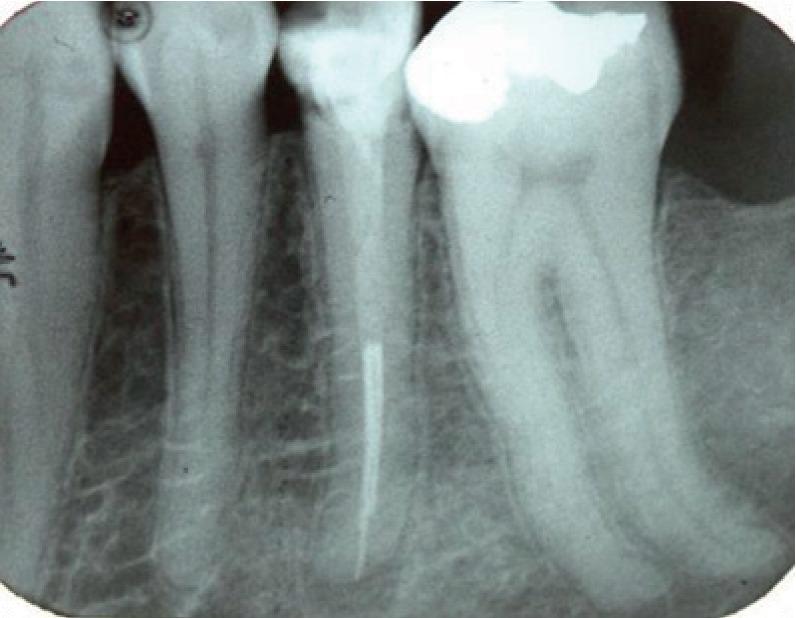

Radiculomegaly is a rare condition involving elongated tooth roots. This condition has significant clinical implications and has been associated with syndromes such as oculofaciocardiodental syndrome. However, only a few nonsyndromic cases of radiculomegaly have been reported. Here, we report a case of nonsyndromic radiculomegaly in a Saudi individual. A subsequent review of the literature suggests endodontic management modalities for individuals with the dental findings demonstrated in the present case.